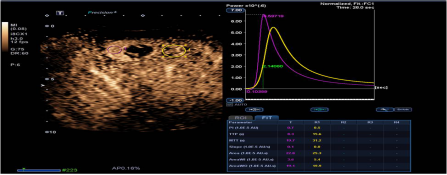

造影定量分析(CHI-Q):

1. 可提供精确的造影剂灌注的定量分析数据用于临床诊断与科研。

2. 自动的ROI 追踪技术可有效消除呼吸运动的影响,提高定量精度。

3. 造影成像原始数据存储可以方便实现在机和脱机的定量分析